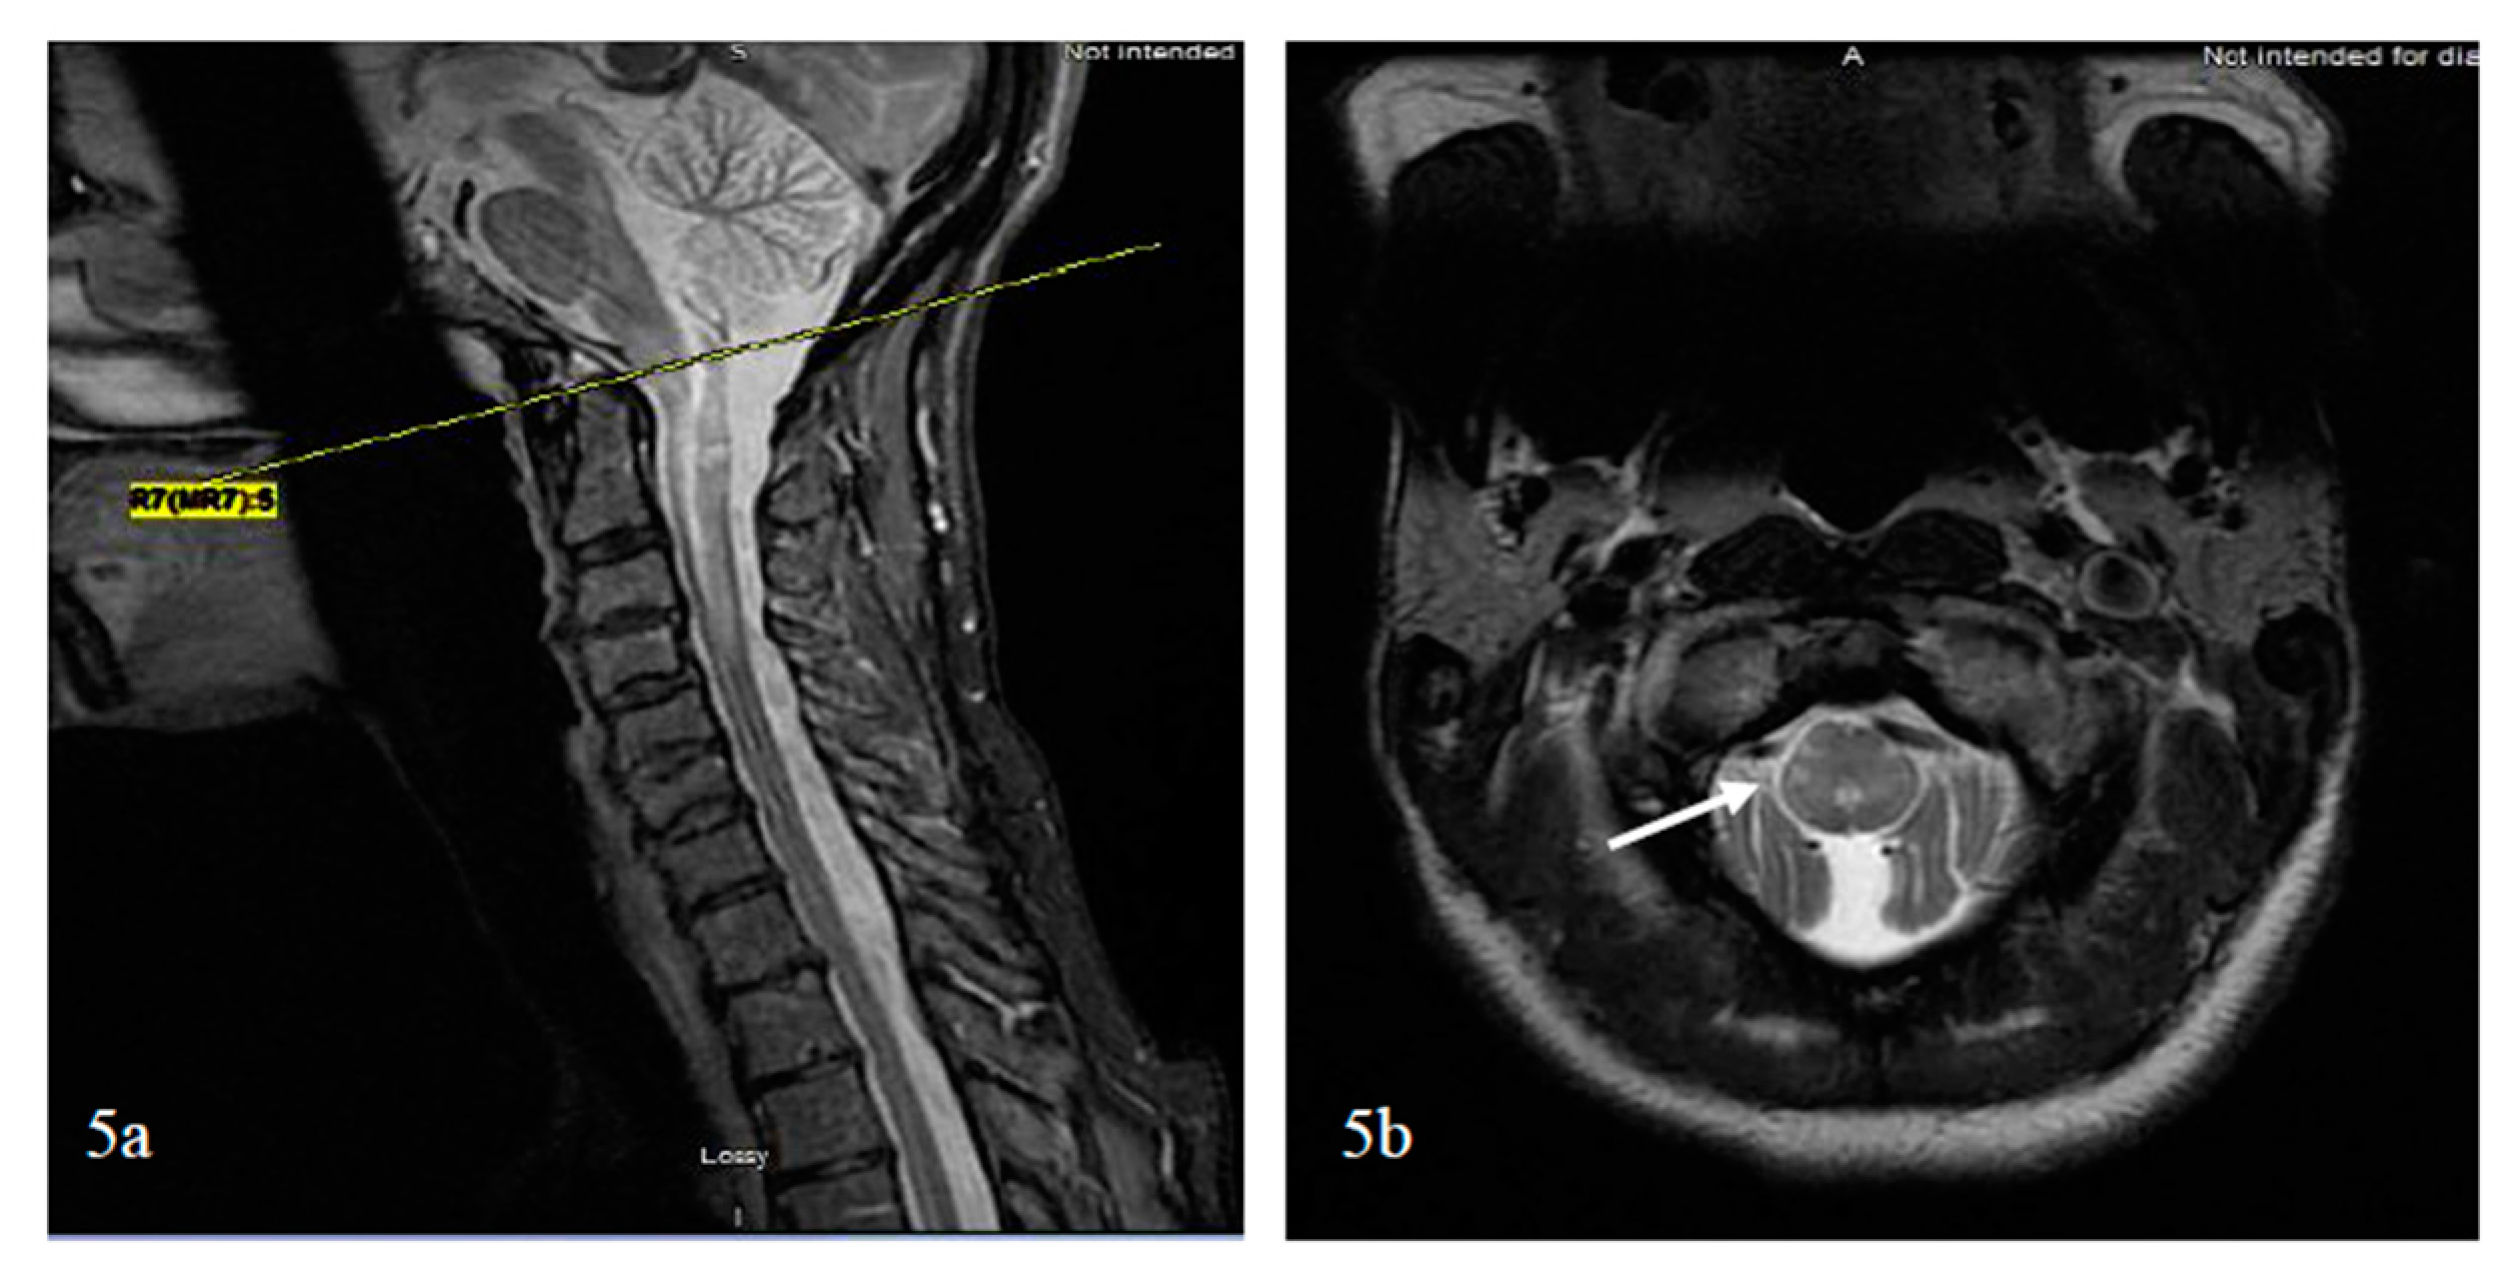

- Cai, W.; Tan, S.; Zhang, L.; Shan, Y.; Wang, Y.; Lin, Y.; Zhou, F.; Zhang, B.; Chen, X.; Zhou, L.; et al. Linear lesions may assist early diagnosis of neuromyelitis optica and longitudinally extensive transverse myelitis, two subtypes of NMOSD. J. Neurol. Sci. 2016, 360, 88–93. [Google Scholar] [CrossRef] [PubMed]

- Yonezu, T.; Ito, S.; Mori, M.; Ogawa, Y.; Makino, T.; Uzawa, A.; Kuwabara, S. “Bright spotty lesions” on spinal magnetic resonance imaging differentiate neuromyelitis optica from multiple sclerosis. Mult. Scler. 2014, 20, 331–337. [Google Scholar] [CrossRef] [PubMed]

- Pekcevik, Y.; Mitchell, C.H.; Mealy, M.A.; Orman, G.; Lee, I.H.; Newsome, S.D.; Thompson, C.B.; Pardo, C.A.; Calabresi, P.A.; Levy, M.; et al. Differentiating neuromyelitis optica from other causes of longitudinally extensive transverse myelitis on spinal magnetic resonance imaging. Mult. Scler. 2016, 22, 302–311. [Google Scholar] [CrossRef] [PubMed]